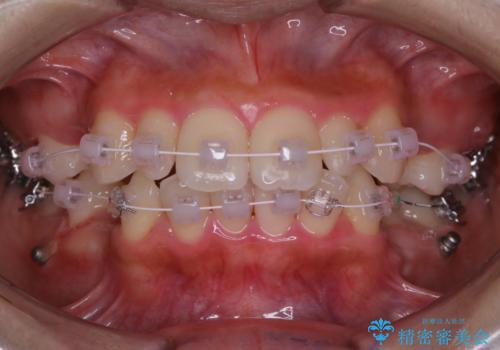

ワイヤー矯正中のクリーニング PMTC

- ワイヤー矯正中にクリーニングを行いたいとのことで来院されました。PMTC60分コースでと歯磨き指導も行いました。

ワイヤー矯正中はブラッシングが難しくなるため、磨き残しが多くなることがあります。適切な道具を使って、適切なブラッシング方法を習得することで、磨き残しを減らすことができます。

また、矯正で歯の移動があると今までなかったところに隙間が出てきたり、ガタつきが解消されてきたりすることで、お口の中の環境が変わります。そのため、定期的に専門的な機械・材料を使用したProfessinnalcleaning(pmtc)を行うことがおススメです。